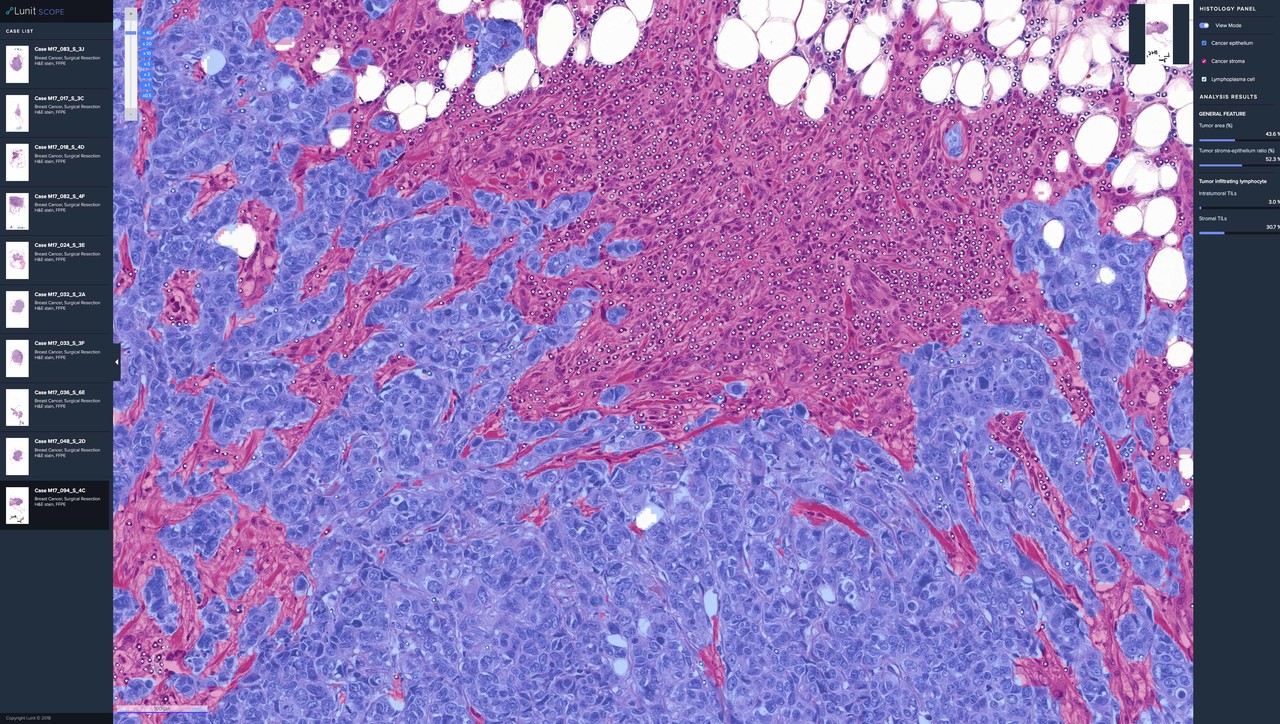

이번 연구는 비소세포폐암(Non-Small Cell Lung Cancer, NSCLC) 환자 518명을 대상으로 인공지능 바이오마커인 루닛 스코프 IO를 활용해 환자별 면역학적 형질에 따라 각각 면역 활성(Inflamed), 면역 제외(Immune-Excluded), 면역 결핍(Immune-Desert) 등 3그룹으로 나눈 뒤 면역항암제의 반응 여부를 예측했다.

그 결과 종양이 일정 크기 이상으로 커지지 않고 환자가 생존한 기간을 뜻하는 무진행생존기간(PFS, Progression Free Survival)과 환자군의 전체생존율(Overall Survival, OS)에서 각 그룹별로 유의미한 임상적 결과를 확인했다. 특히 연구에서는 루닛 스코프 IO가 기존 바이오마커인 PD-L1을 효과적으로 보완할 수 있는 가능성도 확인됐다.

연구에서는 PD-L1 양성발현 점수(Tumor Proportion Score, TPS)를 각각 50% 이상, 1~49%, 0% 등 3그룹으로 구분한 뒤, 루닛 스코프 IO를 통해 각 그룹을 다시 면역 활성과 비활성으로 세분화했다. 일반적으로 PD-L1 TPS 50% 이상은 면역항암제 반응이 예측된다는 점에서 문제될 것이 없으나, 1~49% 그룹에서는 반응성 예측율이 낮다는 단점이 있었다.

하지만 루닛 스코프 IO를 활용해 TPS 1~49% 그룹을 분석한 결과, 면역 활성 그룹에서 전체 환자 약물 투약 후 종양 위축 정도를 나타내는 객관적반응률(Object Response Rate, ORR)과 무진행생존기간(PFS)이 비활성 그룹에 비해 크게 높은 것으로 나타났다. 이는 루닛의 AI 바이오마커가 기존 PD-L1의 약점인 TPS 1~49% 환자군의 치료 반응을 더욱 정확하게 예측할 수 있는 새로운 바이오마커가 될 수 있음을 의미한다.